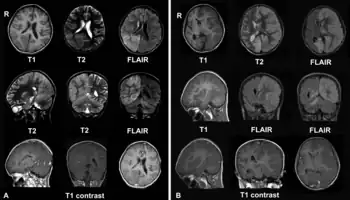

A. Diciembre de 2008, el paciente ingresa con cefalea y epilepsia partialis continua. Hay lesiones con inflamación local en los lóbulos parietal y occipital del hemisferio derecho del cerebro y del hemisferio derecho del cerebelo.

B. En abril de 2009, el mismo paciente, ahora en estado de coma con epilepsia partialis continua. Hay deterioro debido a la encefalitis - existe compromiso del hemisferio cerebral izquierdo con edema cerebral severo y desplazamiento de las estructuras de la línea media.